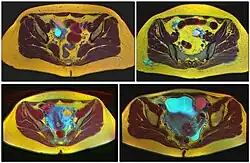

Ovarian cysts are usually diagnosed by pelvic ultrasound, CT scan, or MRI, and correlated with clinical presentation and endocrinologic tests as appropriate.[15] Ultrasound is the most important imaging modality, as abnormalities seen in a CT scan sometimes prove to be normal in ultrasound.[5][8] If a different modality is needed, then MRIs are more reliable than CT scans.[5]

Polycystic ovarian syndrome involves the development of multiple small cysts in both ovaries due to an elevated ratio of leutenizing hormone to follicle stimulating hormone, typically more than 25 cysts in each ovary, or an ovarian volume of greater than 10 mL.[19]

Larger bilateral cysts can develop as a result of fertility treatment due to elevated levels of HCG, as can be seen with the use of clomifene for follicular induction, in extreme cases resulting in a condition known as ovarian hyperstimulation syndrome.[20] Certain malignancies can mimic the effects of clomifene on the ovaries, also due to increased HCG, in particular gestational trophoblastic disease. Ovarian hyperstimulation occurs more often with invasive moles and choriocarcinoma than complete molar pregnancies.[21]